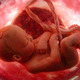

Desenvolvimento da Genitália Externa

A genitália, ainda indiferenciada nesse ponto, é formado por um tubérculo genital, pregas uretrais e uma prega anal. Nos homens, os andrógenos determinam a elongação do tubérculo, formando o falo, e o fechamento do sulco uretral, originando a uretra peniana. O estrogênio, nas mulheres, faz do tubérculo o clitóris e da prega uretral os lábios menores.

• Final da Formação da Vagina

Nesse período, a vagina está completamente canalizada. Tem origem dupla, sendo a parte superior derivada do canal uterino ou seja, do ducto de Müller, e a parte inferior da porção pélvica do seio urogenital.

• Fim do desenvolvimento

Fim do desenvolvimento